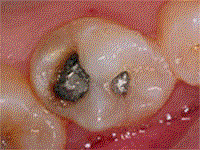

También se ha podido reemplazar las amalgamas. Este tipo de material logra una ecxelente estética y función cuando la cavidad de caries es pequeña.

Si las caries son grandes puede ser reemplazada por incrustaciones de resina termopolimerizadas o de cerámica preformada, como muestra la secuencia.Y no hay duda que el avance en este campo continuará mejorando los materiales y bajando los costos de dichas prestaciones, para beneficio de nuestros pacientes y el propio.